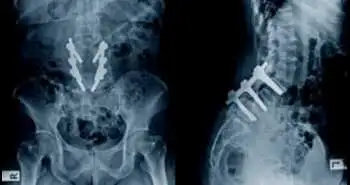

У дане дослідження включили 109 пацієнтів. Дані рентгенографічного дослідження оцінювали на підставі рентгенограм всього хребта (включаючи такі показники, як грудний кіфоз, кут Кобба, нахил таза, поперековий лордоз, ураження таза). Клінічні дані оцінювали з використанням візуальної аналогової шкали болю (ВАШ), індексу інвалідизації Освестрі (ODI), опитувальника для оцінки якості життя, пов'язаного зі здоров'ям, Товариства дослідження сколіозу (SRS-30) і короткого опитувальника оцінки стану здоров'я з 12 пунктів (SF-12). Оцінювали ступінь лістеза нижче місця артродеза і висоту міжхребцевого диска.

Дані рентгенографічного дослідження 46 пацієнтів аналізували в середньому через 17,4 року. Перед хірургічним втручанням середній кут Кобба становив 58 °, середня корекція склала 40,1%  з втратою  5,3 ° за результатами заключного візиту подальшого спостереження. До кінця наступного спостереження відзначалося виражене збільшення грудного кіфозу і поперекового лордозу.

В ході проведеного дослідження встановлено, що у пацієнтів з юнацьким ідіопатичним сколіозом хірургічне втручання з використанням транспедикулярної фіксації забезпечує поліпшення довгострокових результатів за даними клінічних і рентгенографічних досліджень.